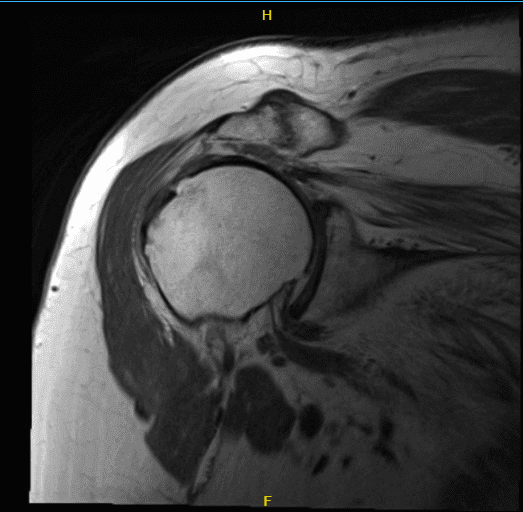

For MRI right shoulder, large full-thickness tear of supraspinatus tendon. Tear excluding its posterior tendon that is partially torn. There is moderate muscle. Partial tear of infraspinatus tendon. Complete tear of subscapularis tendon that is scarred to the capsule associated with near complete muscle atrophy.

Medial dislocation of long headed biceps tendon with tendinosis and partial tear. Mild glenohumeral and moderate acromioclavicular joint degenerative disease. Moderate subacromial subdeltoid bursitis.